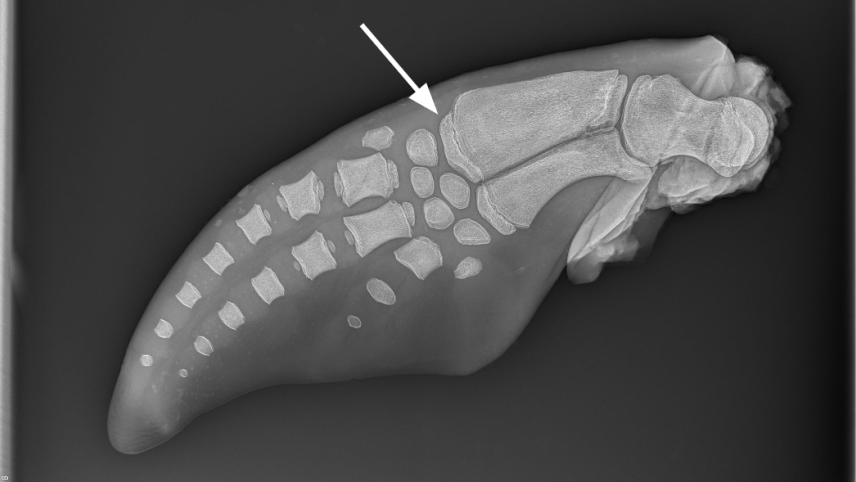

An x-ray of a dolphin flipper. An arrow indicates a slightly separated section of bone at the end of another bone.

A pectoral flipper radiograph taken of a bottlenose dolphin estimated to be 1.92 years old. We give bone maturation scores to 16 locations on the flipper, then enter the scores into an equation to estimate the animal’s age. The arrow is pointing to one such area, a center of bone formation on the end of the radius. We score this area based on its width in comparison to the radius, as well as its percentage of fusion to the radius. The image was taken using x-ray equipment at the South Carolina Aquarium. (Image credit: Sophia Brice)